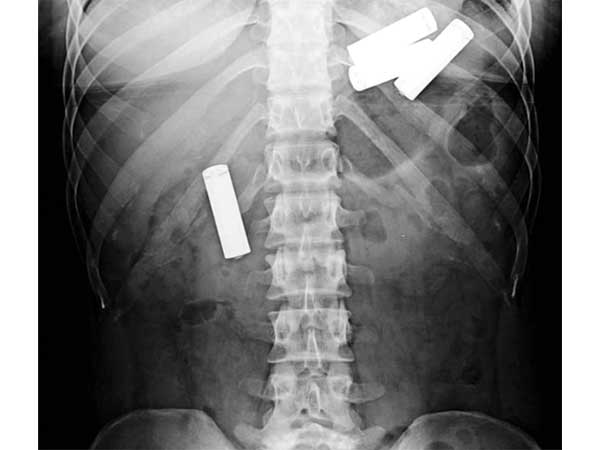

Pen

A 76-year-old woman who complained of severe stomach ache was admitted into a hospital. Her x-ray report revealed that she had a pen inside her body. It was there safe for 25 years. Once they removed it, the doctors were amused to see the pen still in a writing condition.